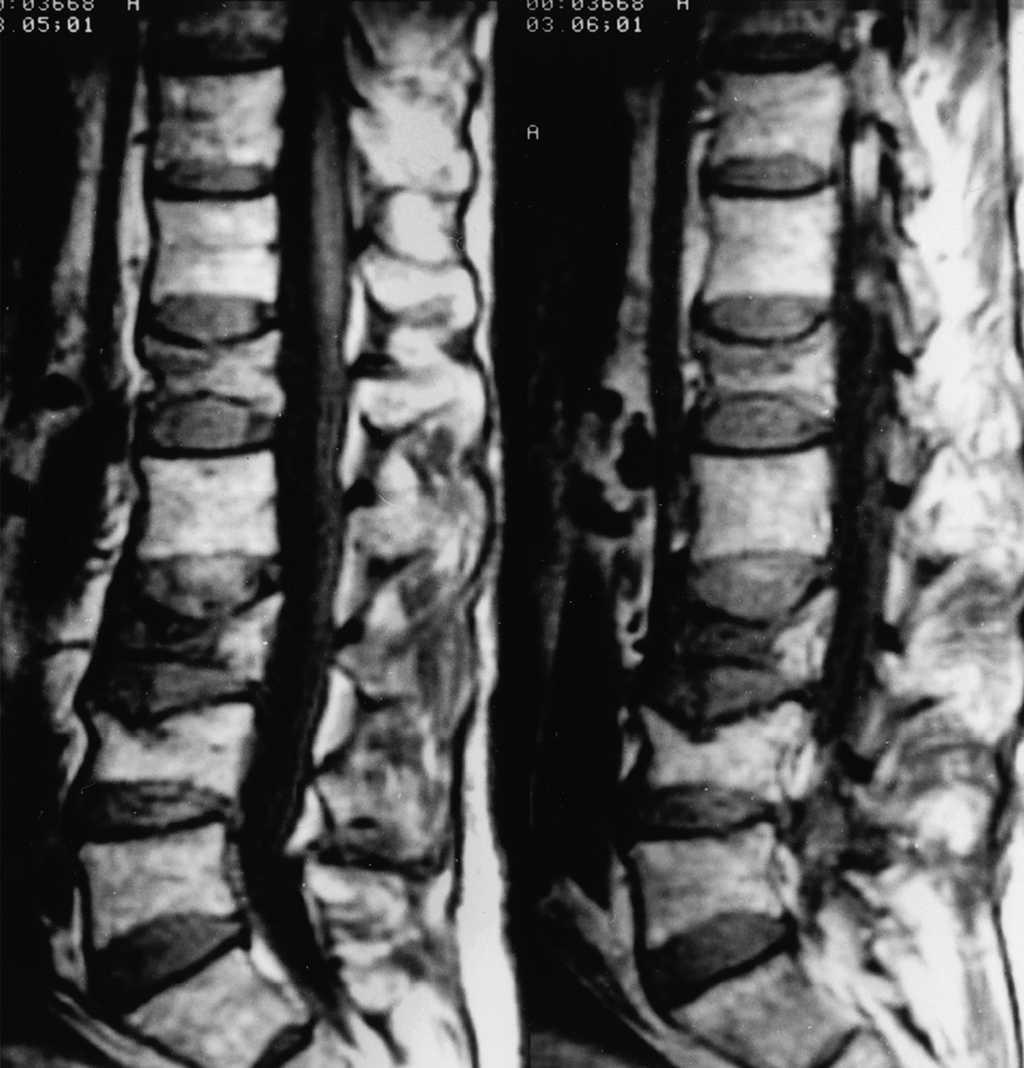

Fractura aplastamiento vertebral por fragilidad

La fractura vertebral por compresión (aplastamiento vertebral) es considerada la fractura osteoporótica más común. Puede causar dolor agudo y/o crónico, aunque a menudo pasa desapercibida y no es diagnosticada. Constituye un factor de riesgo independiente de nuevas fracturas vertebrales y de otras localizaciones, y se asocia a un exceso de mortalidad. En la mayoría de los pacientes, el dolor remite en unas semanas, aunque en un porcentaje de ellos el dolor puede persistir durante más tiempo con discapacidad o incluso requerir ingreso hospitalario para controlar el dolor. FMC, agosto de 2020